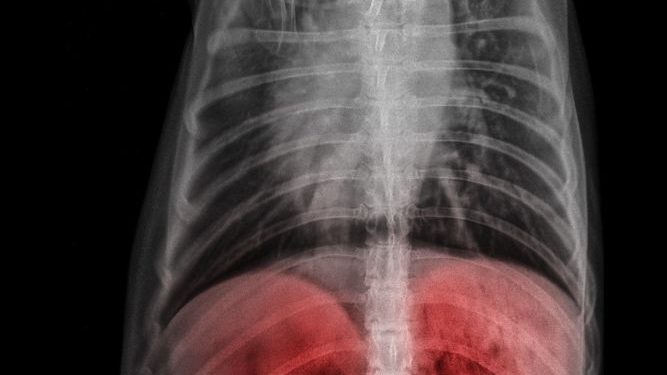

A liver tumor is an abnormal growth that starts on the liver. It is usually benign (non-cancerous), but it can also be malignant. Benign tumors do not cause any symptoms unless they grow too big. They do not spread to other parts of the body and they usually do not cause problems if they are removed surgically.

The first step in diagnosing a liver tumor is to take a detailed medical history. The doctor may order blood tests and imaging to look for lesions. This is done to determine the type and stage of the liver tumor. Then, the doctor will decide the best way to treat the lesion.